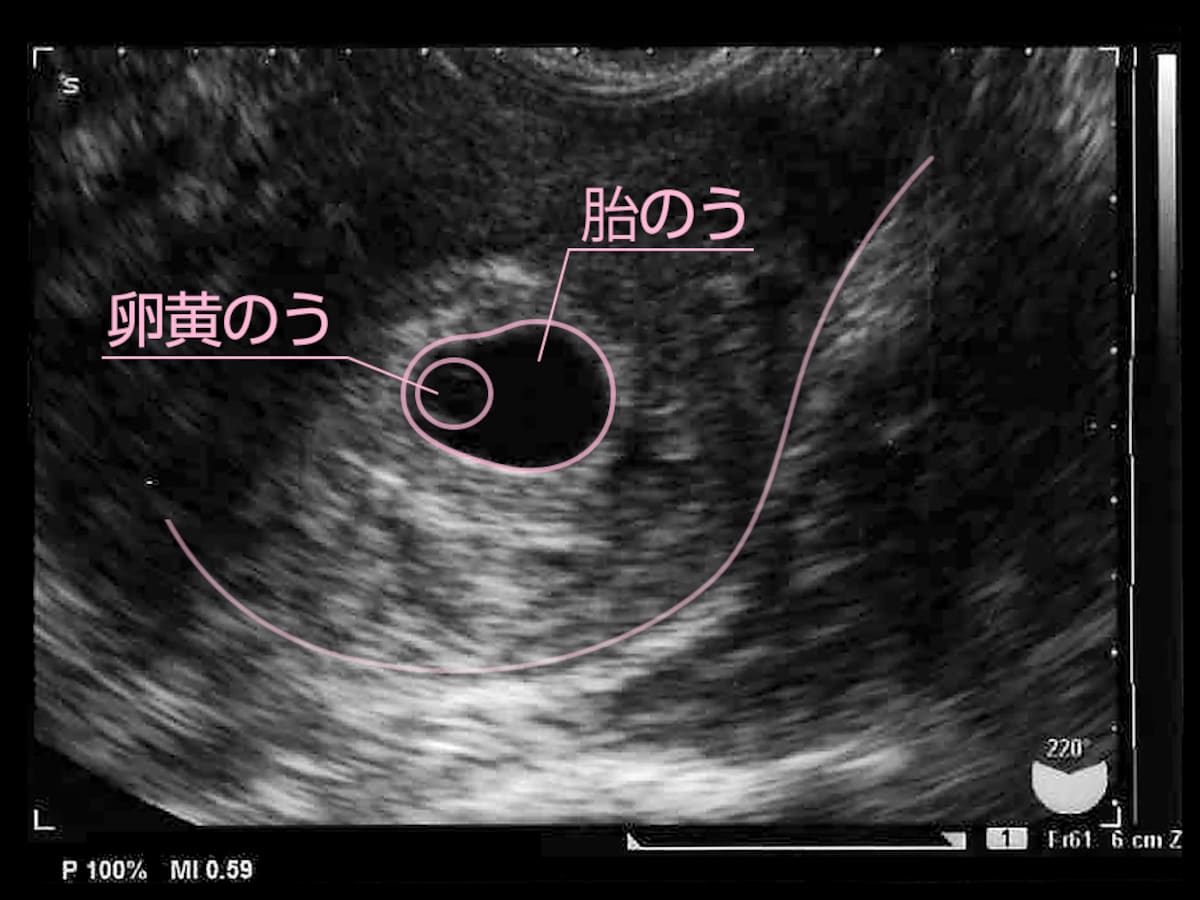

胎嚢と胎芽 確認できる時期はいつごろ 見えない時の原因など 大きい 小さい 形 専門家 河井助産師監修

5週 体外受精での妊娠は胎嚢が小さい 論文を確認してみた Oh マイライフハック

胎嚢が小さい原因は 妊娠5週や6週の平均的なサイズは こそだてハック